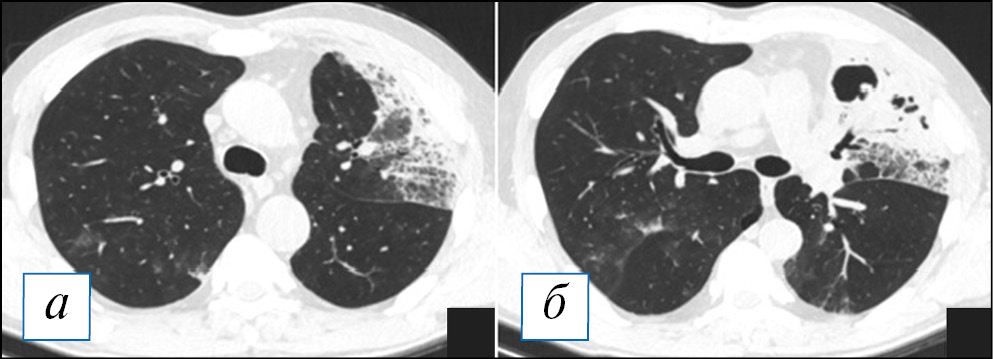

При проведении КТ органов грудной клетки отмечается уплотнение, чаще в виде консолидации или по смешанному типу, в сочетании с «матовым стеклом» пораженной части легкого, которая может быть несколько увеличена в размерах (рис. 2, Б), что объясняется скоплением экссудата и отеком легочной паренхимы по типу «выбухающей борозды». На фоне уплотнения быстро происходит деструкция легочной ткани в виде множественных очагов или более обширных участков; в начале этого процесса в полостях распада можно наблюдать некоторое количество содержимого с горизонтальным уровнем; секвестры нехарактерны (рис. 2). Внутренняя стенка полостей имеет четкий контур, что объясняется дренированием содержимого через бронхи, которые в ряде случаев прослеживаются (рис. 3). Может отмечаться выраженная реакция плевры, с развитием выпота или даже эмпиемы и пиопневмоторакса, особенно при формировании свища [8, 9, 40]. Негативными последствиями некротизирующей пневмонии может являться формирование фиброза с бронхоэктазами, персистирование полостей распада при отсутствии их спадения, а также облитерация плевральной полости на уровне воспалительного процесса [39].

Рис. 2. Компьютерная томография органов грудной клетки в аксиальной проекции (а–г). Двусторонняя полисегментарная пневмония. С обеих сторон в легких, больше справа, имеются инфильтраты, на фоне которых просматриваются полости различного размера без жидкостного содержимого. Незначительный пневмомедиастинум. [Изображения из архива авторов]. / Fig. 2. Chest CT, axial projection (а–г). Bilateral polysegmental pneumonia. On both sides in the lungs, more to the right, there are infiltrates and cavities of various sizes without liquid content. Minor pneumomediastinum. [Images from the authors’ archive].

Рис. 3. Компьютерная томография органов грудной клетки в аксиальной проекции (а, б). Пневмоническая инфильтрация в верхней доле слева с деструкциями. Имеются участки по типу «шальной исчерченности» в сочетании с консолидацией, на фоне которой обнаруживаются разнокалиберные полости распада без содержимого, наружный их контур не прослеживается. [Изображения из архива авторов]. / Fig. 3. Chest CT, axial projection (а, б). Pneumonic infiltration in the upper lobe on the left with destructions. There are areas of a «crazy paving» sign in combination with consolidation, against the background of which one can see destructive cavities of various sizes without content, their outer contour is not traced. [Images from the authors’ archive].